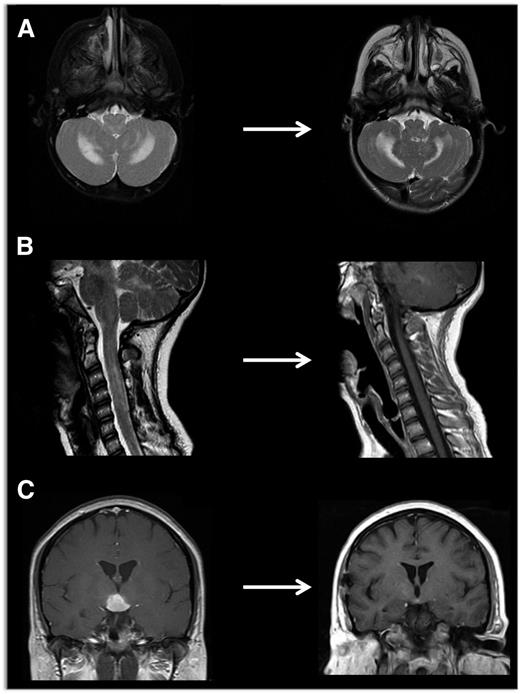

Evaluating disease activity and response to therapy

Neuroimaging of LCH lesions. These examples demonstrate typical manifestations of LCH CNS and spinal cord lesions. (A) Brain MRI demonstrates T2-hyperintensity in cerebellum classic for LCH neurodegenerative syndrome. In this case, the patient had radiologic and clinical response to treatment with cytarabine. (B) Spinal MRI demonstrates significant spinal cord lesions. This is a somewhat atypical case of a 13-year-old girl who had marginal response to cytarabine, then clofarabine. BRAF-V600E was detected in cells from the CSF, and the patient ultimately had radiologic and clinical response to vemurafenib. (C) Brain MRI demonstrates a pituitary mass classic for LCH, though differential diagnosis also includes germinoma, lymphoma, and pituitary hypophysitis. In this case, the lesion was biopsy proven to be LCH, and the patient responded to cytarabine therapy.

Neurodegenerative CNS LCH